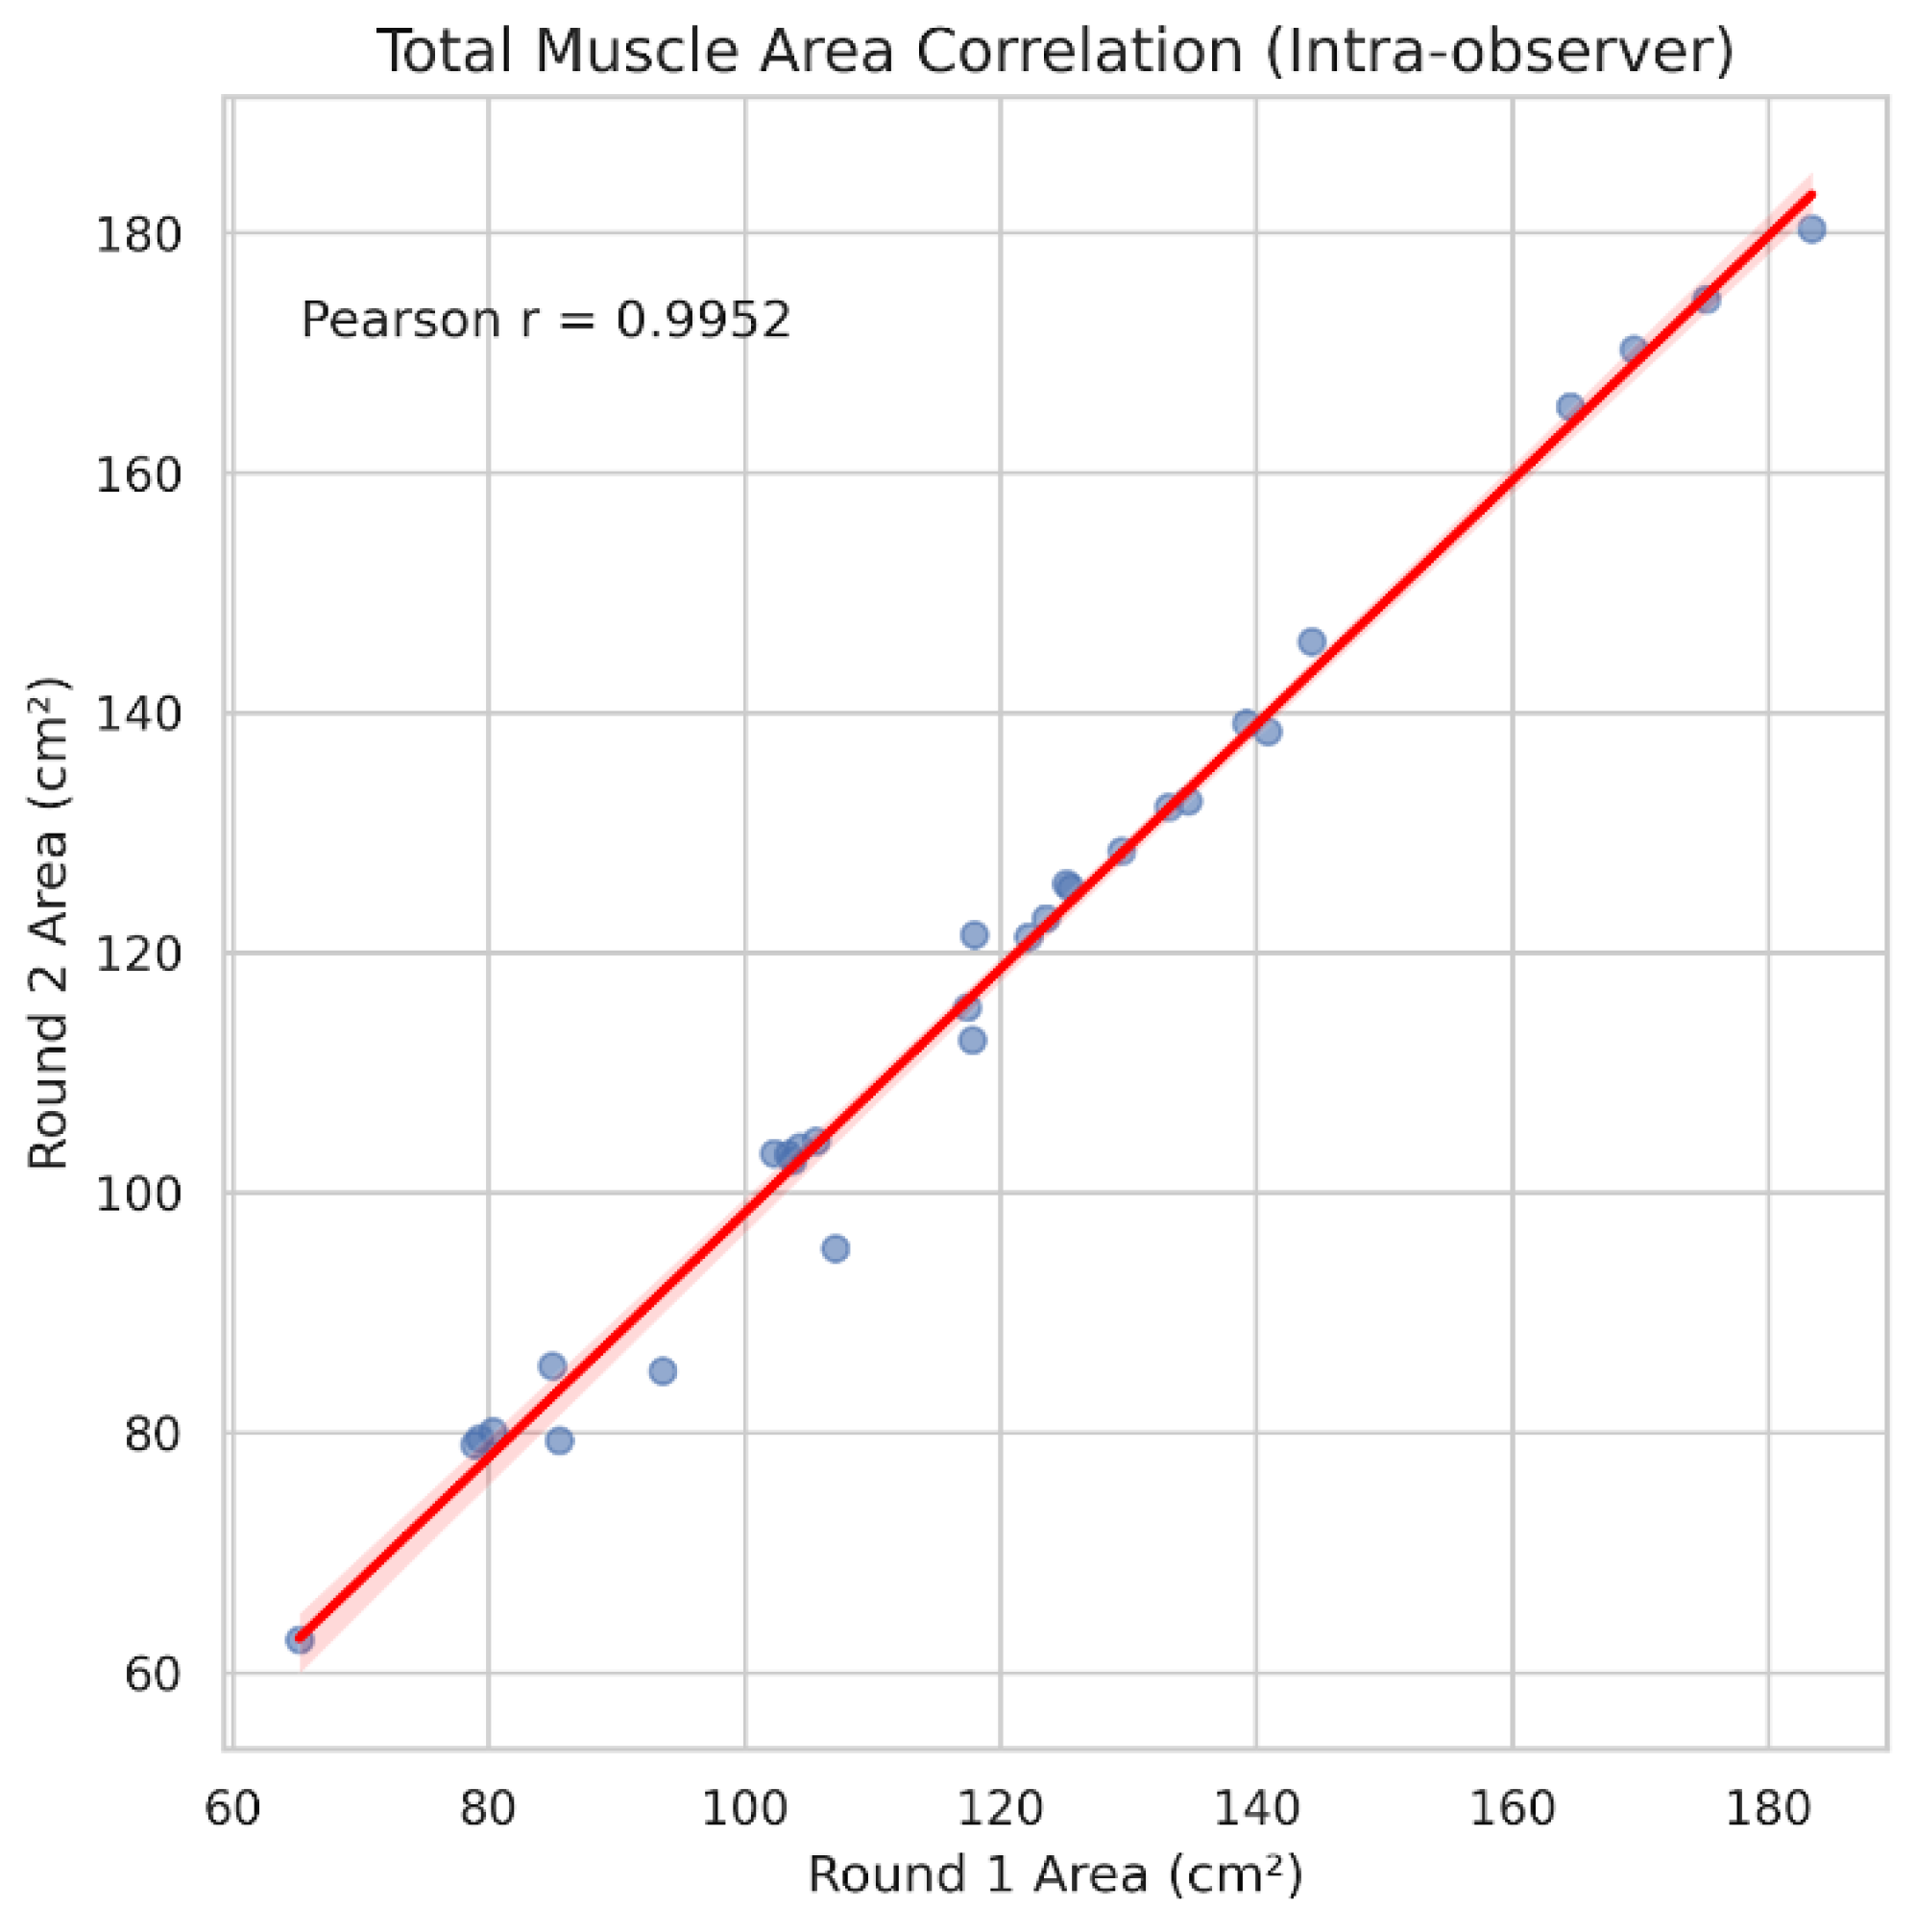

3.4. Intra-Observer Reliability and Time Efficiency

| Metric | Pearson r | MAE | Mean bias (round 2 - round 1) |

|---|---|---|---|

| Total muscle area (cm²) | 0.995 | 1.98 | -1.31 |

| Total mean attenuation (HU) | 0.995 | 0.74 | +0.56 |